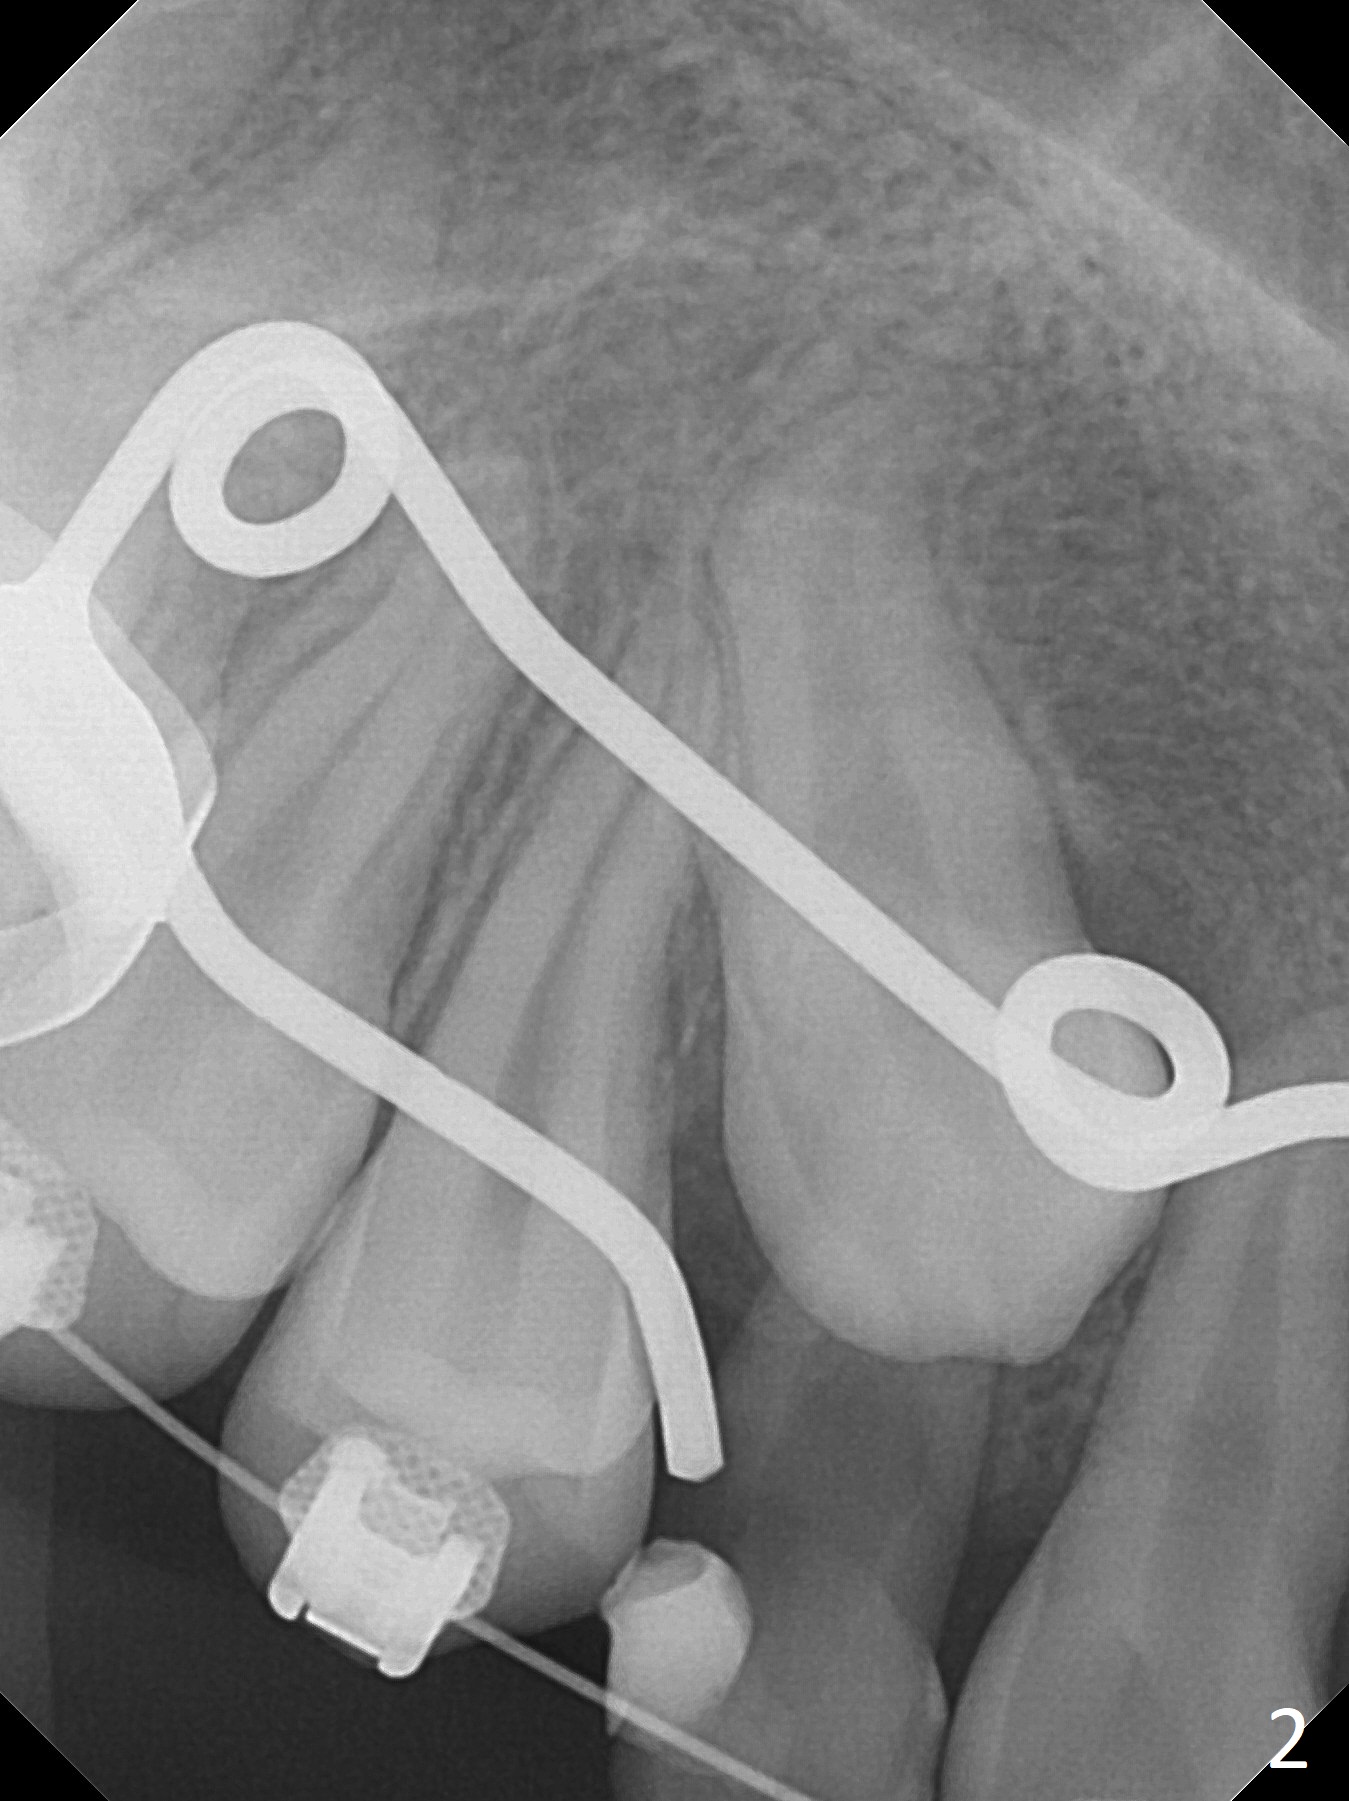

A 13-year-old woman has an impacted canine (Fig.1 (6)) and retained deciduous one (C). After initiation of orthodontics, she returns for surgical access to the impacted canine and placement of device to facilitate eruption (Fig.2,3). Incision is made buccal (Fig.4), but there is no tooth buccal (Fig.5). Extraction of the deciduous canine does not reveal the impacted one (Fig.6), but there is palatal elevation (*). Palatal access shows the impacted tooth (Fig.7) and allows placement of a retraction device (Fig.8). Careful clinical exam and CBCT are necessary diagnostic steps.